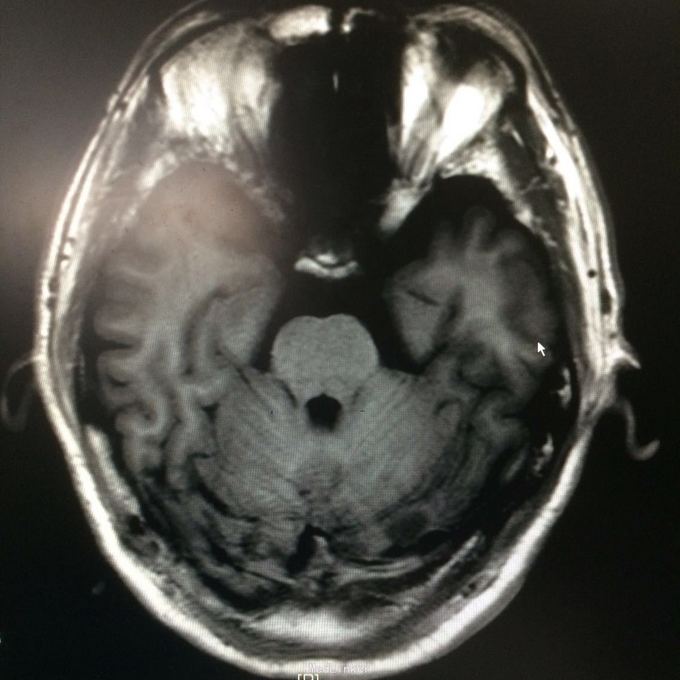

主诉:头晕头痛2年 病史:2年前无明显诱因出现头痛,呈刺痛,程度较重,伴头晕、天旋地转感,1年前查头颅MR提示:左侧小脑半数囊性病变,考虑血管母细胞瘤

查体:神志清楚,病理证阴性 辅助检查:头颅MR提示左侧小脑半数后部囊状占位灶,考虑良性病变。

诊断:左侧小脑血管母细胞瘤 处理:行左侧小脑占位病变切除术,术后病理提示:符合血管母细胞瘤。